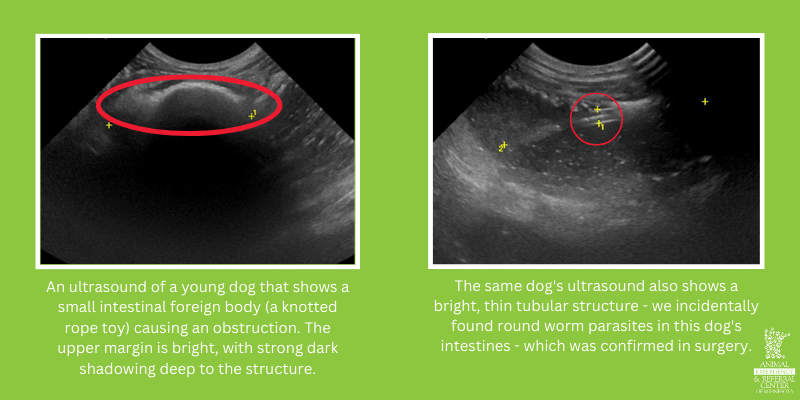

Two images of abdominal ultrasound findings. The left ultrasound shows an ultrasound of a young dog that shows a small intestinal foreign body (a knotted rope toy) causing an obstruction. The upper margin is bright, with strong dark shadowing deep to the structure. The right ultrasound is the same dog's ultrasound also shows a bright, thin tubular structure - we incidentally found round worm parasites in this dog's intestines - which was confirmed in surgery. Both ultrasounds from Animal Emergency & Referral Center of Minnesota.

1. Gastroenteritis or Foreign Body Obstructions

What if a Foreign Body is Spotted?

Foreign bodies are diagnosed less often via ultrasound, but still commonly. After all, random objects are often pretty noticeable during an ultrasound! Common foreign bodies include trash, toys, small pieces of clothing such as socks or underwear, carpet, or pieces of string.

What the Radiologist Sees:

• Irregular structures in the openings of the gastrointestinal tract.

• Bright appearance in the margin.

• Dark shadowing deeper to the structure.

• Significant dilation (wider or larger) from obstruction leading up to the object